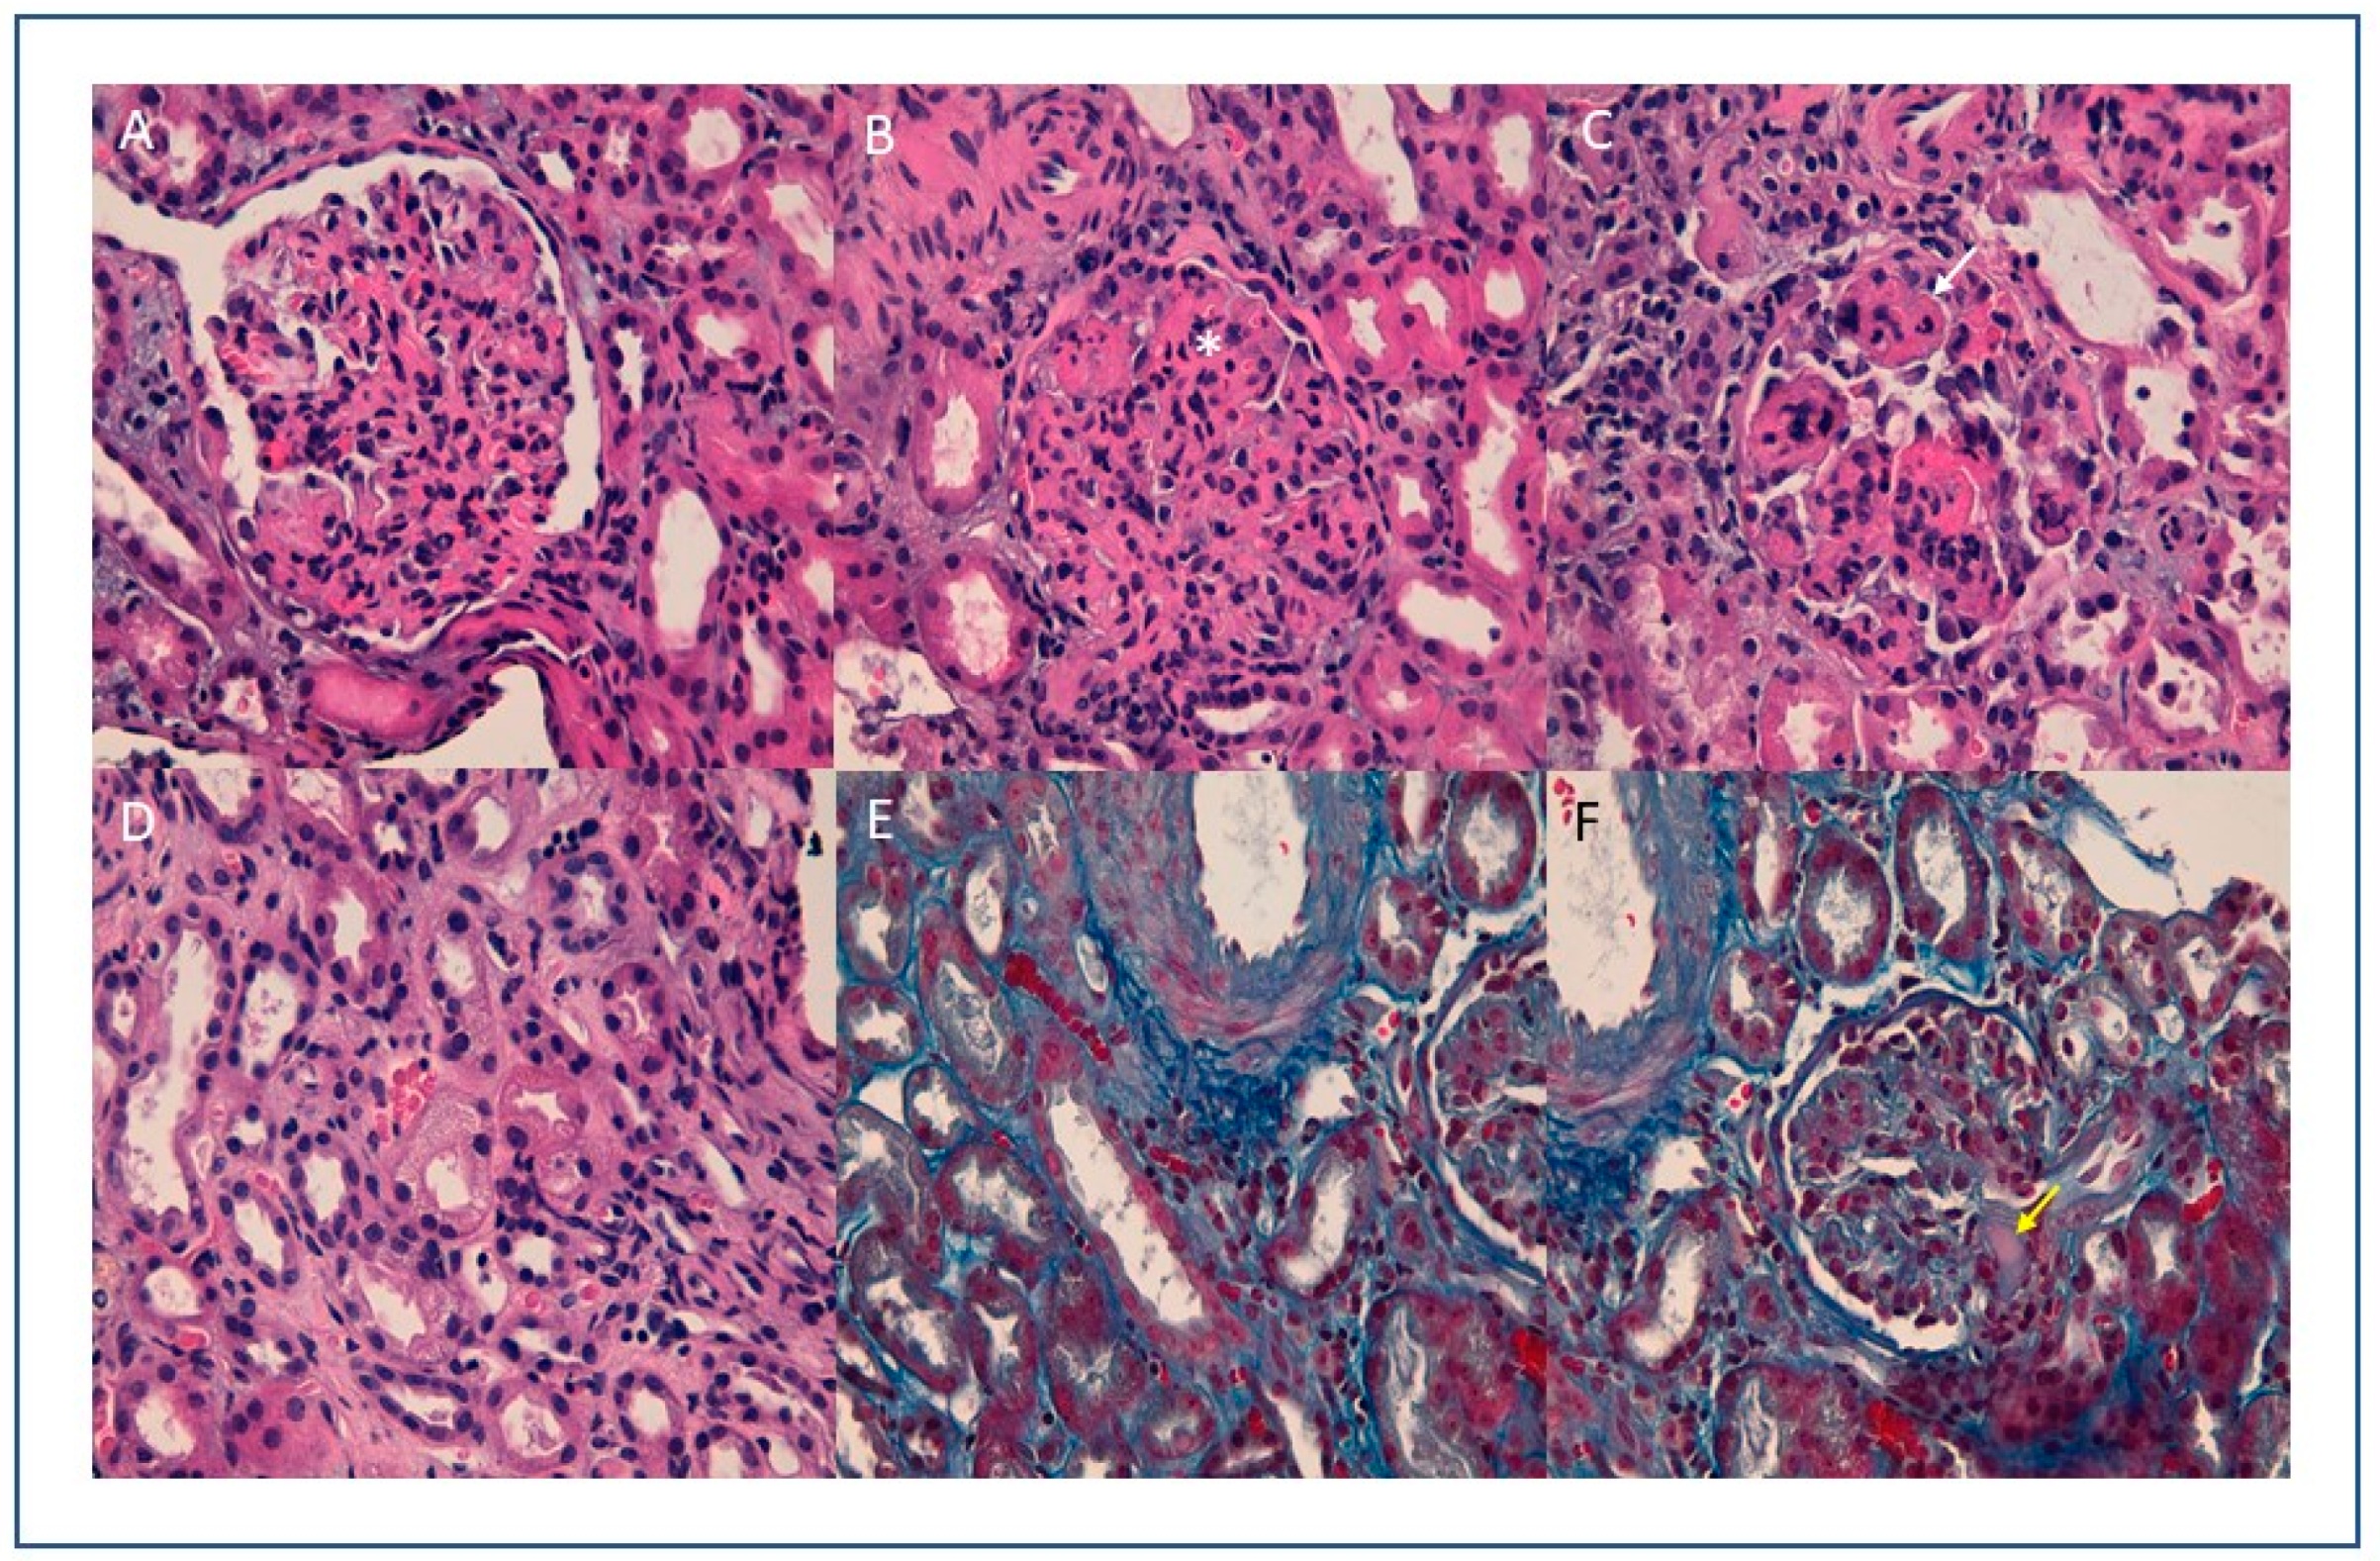

3. Kidney Biopsy Findings